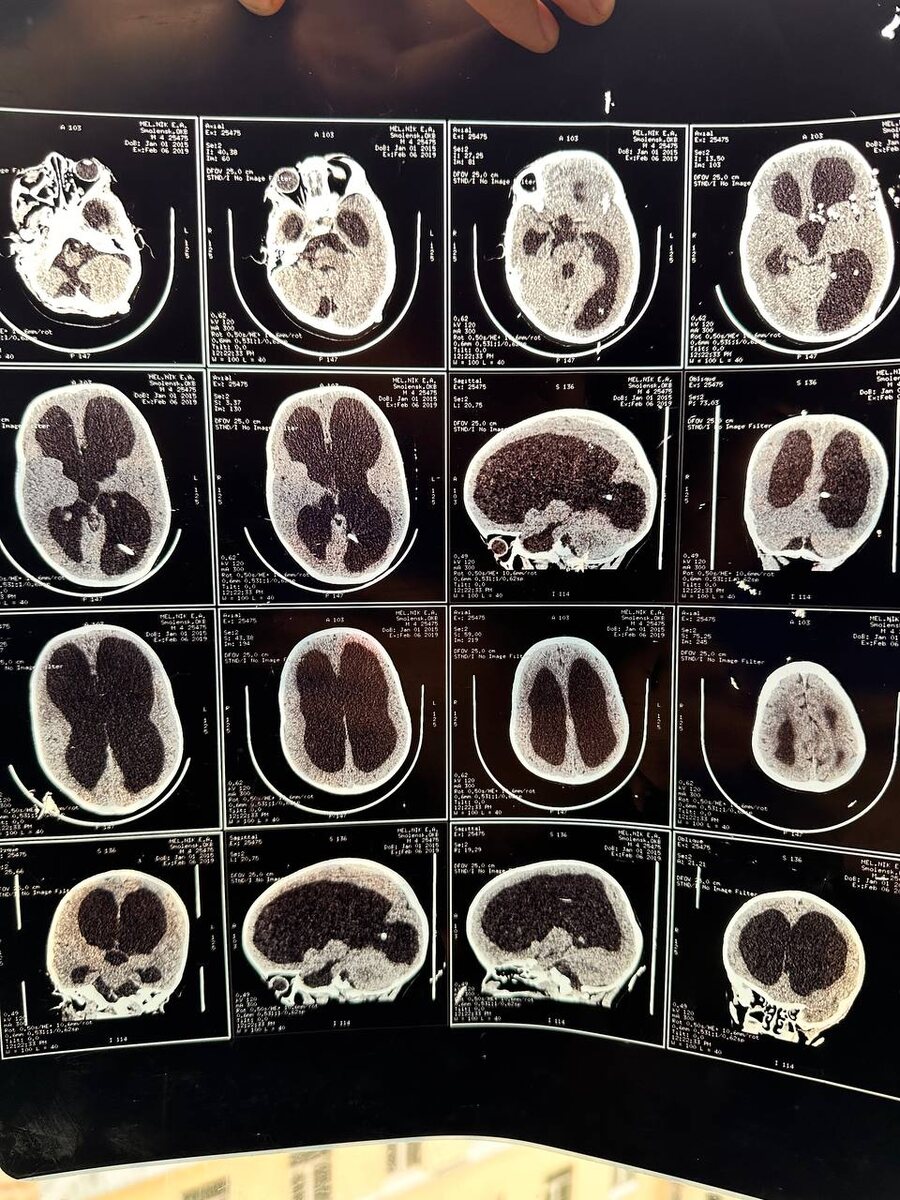

На фото номер 1 снимки головного мозга Елисея, часто обыватели говорят, черные пятна-это мозг. Нет-это ликвор. Мозг это тонкие серые полоски возле основания черепа.

Через 2 месяца после рождения Елисея сделали сложную операцию по шунтированию, его давление в голове было за 220. Состояние его было тяжелым и врачи опасались, что его мозг после снижения давления оборвется и мне запретили его месяц поднимать вертикально.

-«Ваш ребенок здоровый, на фоне наших гидроцефалов. Мы такого не видели, чтоб с таким повреждением мозга ребенок говорил, ходил» в 2 года говорили нейрохирургии

-«Это просто какое-то чудо! Я за 8 лет практики не видел такого» сказал наш оперирующий и лечащий врач-нейрохирург.